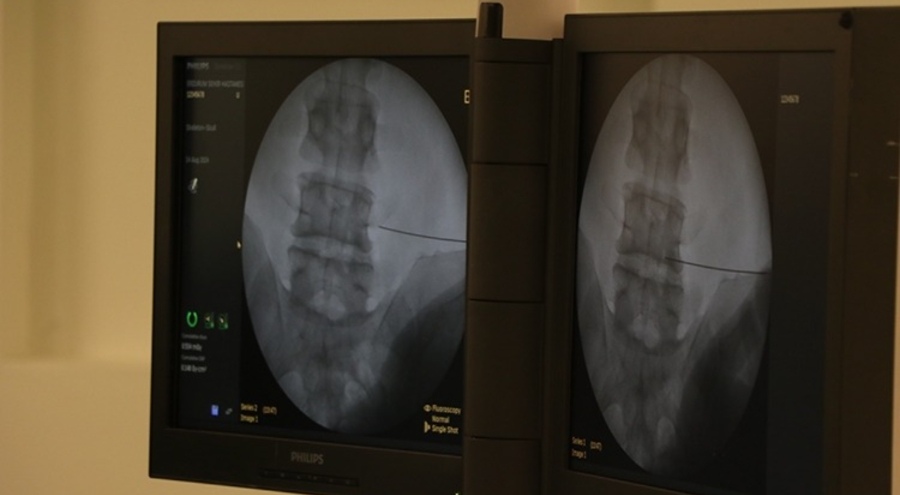

Karadeniz Teknik Üniversitesi (KTÜ) Tıp Fakültesi Genel Cerrahi Anabilim Dalı Dr. Öğretim Üyesi Mehmet Uluşahin, fıtık ameliyatlarının son derece güvenli olduğunu, buna karşın fıtıkla uzun süre yaşamanın ciddi riskler barındırdığını söyledi.

Uluşahin, yaptığı yazılı açıklamada, fıtığın, karın duvarındaki zayıf bir noktadan iç organların dışarı doğru çıkmasıyla oluştuğunu belirtti.

Ağır kaldırma, kronik öksürük, kabızlık, gebelik, obezite ve daha önce geçirilmiş ameliyatların fıtık gelişimini kolaylaştıran başlıca nedenler olduğuna işaret eden Uluşahin, fıtıkların başlangıçta basit şişlik gibi algılanabildiğini, zamanla büyüyen fıtıkların ise ciddi sağlık sorunlarına yol açabildiğini ifade etti.

"Günümüzde fıtık ameliyatlarının açık ve laparoskopik (kapalı) yöntemlerle başarıyla uygulanıyor. Cerrahi yöntem hastaya özel olarak planlanıyor. Günümüzde fıtık ameliyatları son derece güvenlidir. Buna karşın fıtıkla uzun süre yaşamak ciddi riskler barındırır. Doğru bilgi, doğru zaman ve doğru tedavi hayat kurtarır."